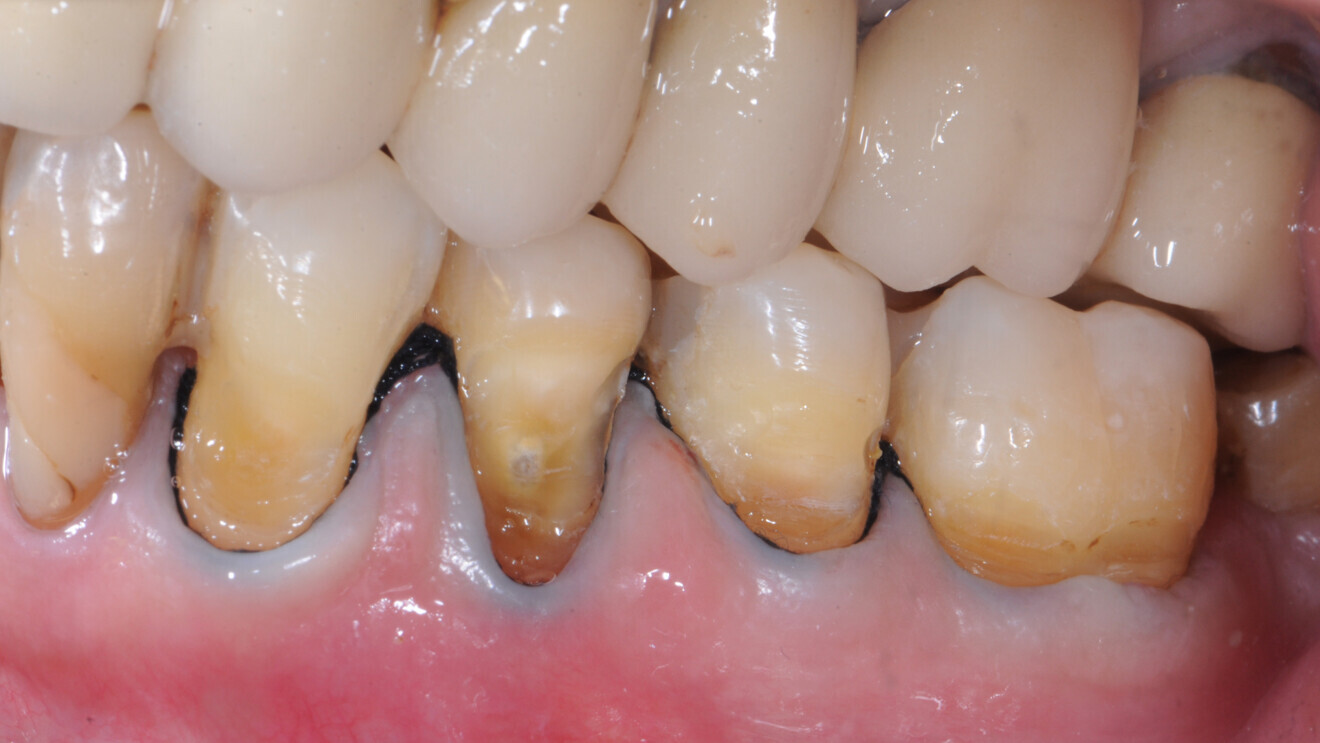

En raison de la perte osseuse parodontale, les patients âgés présentent souvent des espaces interdentaires ouverts qui sont prédisposés aux lésions carieuses radiculaires (Fig. 1). Ces patients doivent veiller à une hygiène de ces espaces au moyen de brossettes interdentaires et d’un dentifrice fluoré.

Fig. 1 : Les racines exposées sont prédisposées au risque carieux ; elles se déminéralisent plus tôt et plus rapidement, car la dentine ou le cément n’est pas protégé par l’émail ou l’alvéole.